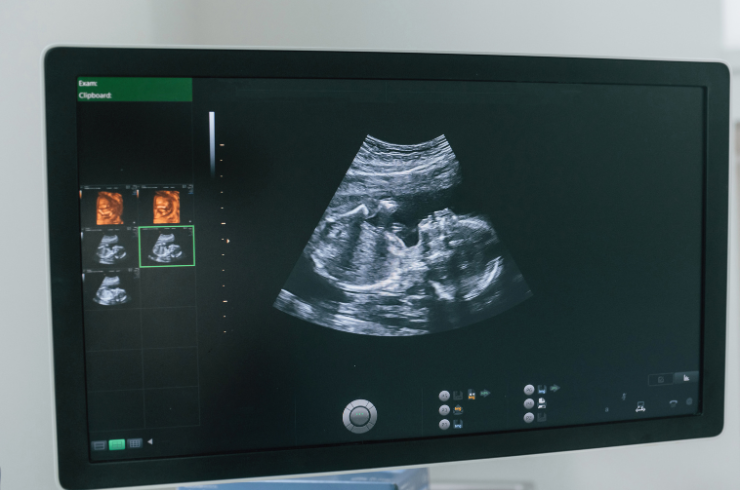

Each scan tells a story. We listen, detect, and guide with precision and care.

Precise Imaging, Healthier Beginnings.